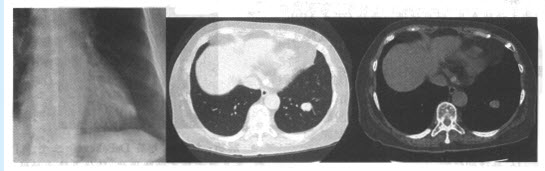

患者,女,35岁。咳嗽1个月余,胸片及CT如下图。

针对上述病例,下列哪种疾病可能性最大()

A:肺癌

B:肺炎性假瘤

C:肺结核球

D:肺错构瘤

E:球形肺炎